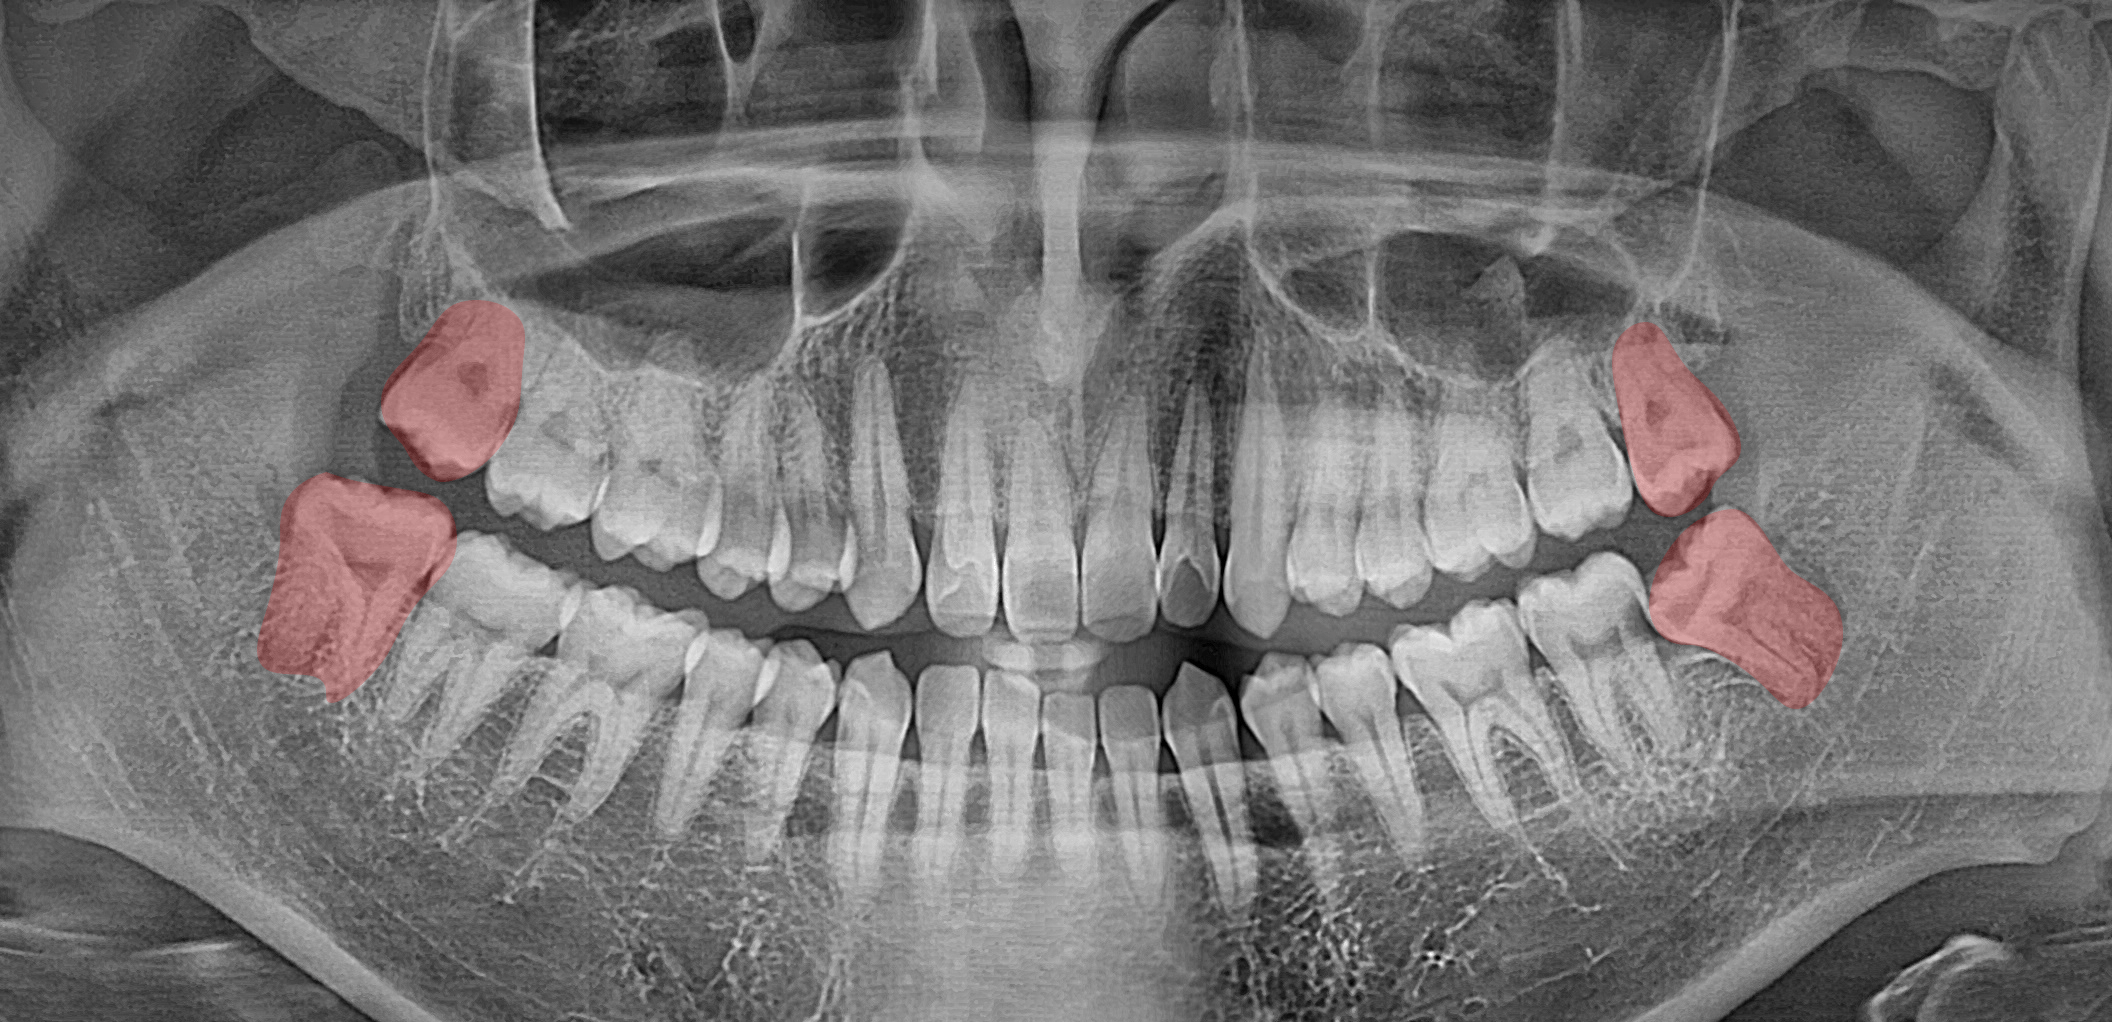

사진 한 장을 보여드리겠습니다.

2024.11.20

Panorama에서

상하좌우 모두 사랑니가

맹출 된 모습을 볼 수 있습니다.

잇몸 위로 일부만

올라온 곳도 있었는데요,

대부분 누워있지 않고

곧게 올라와 있어

발치를 하는데

큰 문제가 없어 보였습니다.

이를 뽑는 과정에서

장애물이 될 것은 없었으나,

충치에 이환되어 예후가

불량한 치아를 확인했습니다.

두 개의 치아가 맞닿아 있는

인접면에서 충치가 시작되어

치조골까지 진행되었습니다.

예후가 매우 불량하였으며

그 앞에 있는 어금니는

보존이 어렵다는 진단입니다.

신경치료를 당장 하더라도

성공률이 낮았기 때문에

발치 가능성이 높았습니다.

그래서 이를 뽑은 후

임플란트를 심기로 결정했습니다.